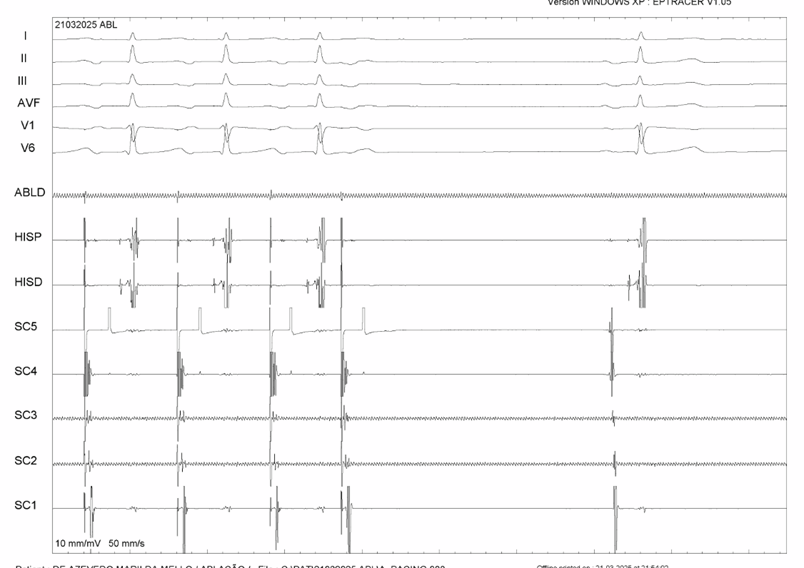

Epicardial Incessant Left Atrial Tachycardia in a 17 yof with two prior failed ablations. Interruption and signals are shown in the comments. There is also a nice image of LAA in RAO with the tacticath in its posterior aspect (between LSPV and LAA) in the epi. @EPeeps_Bot